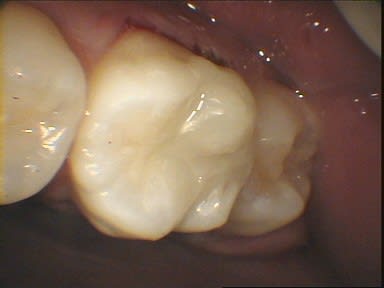

Par comparaison, quelques photos de coiffage pulpaire au CO²

et fin